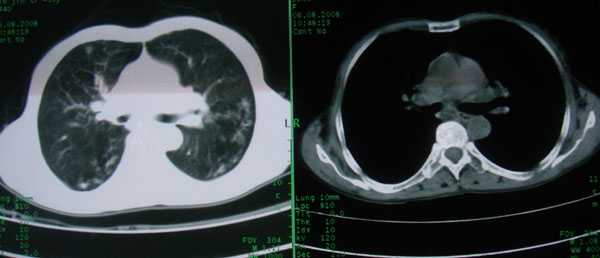

慢性支气管炎伴支气管扩张\\感染

慢性支气管病变并肺部感染。

支持慢性支气管病变并肺部感染。

肺间质性改变 支气管扩张合并感染

慢性支气管炎伴全小型肺气肿、支气管扩张、感染、间质纤维化。